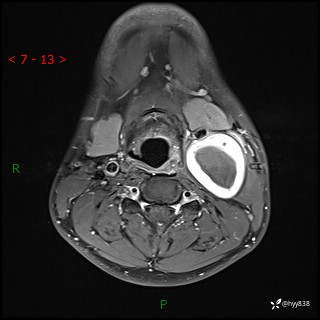

年轻小伙,发现左侧颈部肿物3年余,逐渐增大---结果公布~

现病史:患者约3年前因感冒发现左侧颈部长一肿物,约半个鸡蛋大小,无明显疼痛及其他不适,一直未行特殊处理。3个月前发现左侧颈部肿物变大,随后至当地市第二人民医院耳鼻喉科行左侧颈部彩超示:左侧颈部囊实混合性包块;喉部MPR示:左侧胸锁乳突肌内前方占位,累及左侧喉旁间隙,建议增强扫描。建议手术治疗。患者考虑。随后至我院肿瘤科就诊,行细胞学穿刺示:考虑血管源性肿瘤可能,建议进一步检查。建议至我院口腔科就诊,行颌面部MRI示:左侧颌下腺后方团状异常信号灶,建议增强。建议手术治疗。为求进一步治疗,门诊以“左侧颈部肿物”收入院。 起病以来,患者神志清、精神良好,饮食睡眠良好,大小便正常,体重未见明显变化。

颈部MRI平扫+增强